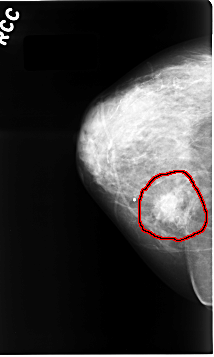

C_0064_1.RIGHT_CC

FILE: C_0064_1.RIGHT_CC.OVERLAY

TOTAL_ABNORMALITIES 1

ABNORMALITY 1

LESION_TYPE CALCIFICATION TYPE AMORPHOUS DISTRIBUTION CLUSTERED

LESION_TYPE MASS SHAPE IRREGULAR MARGINS SPICULATED

ASSESSMENT 5

SUBTLETY 5

PATHOLOGY MALIGNANT

TOTAL_OUTLINES 1

BOUNDARY